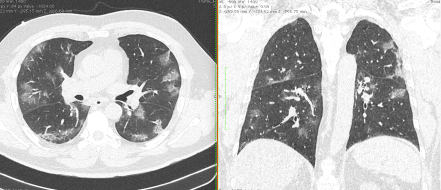

2. Наличие клинических проявлений, указанных в п. 1, в сочетании с характерными изменениями в легких по данным компьютерной томографии (КТ) (см. Приложение 1 настоящих рекомендаций) вне зависимости от результатов однократного лабораторного исследования на наличие РНК SARS-CoV-2 и эпидемиологического анамнеза.

- Изменения при КТ (рентгенографии), типичные для вирусного поражения (объем поражения минимальный или средний; КТ 1 - 2)

- Изменения в легких при КТ (рентгенографии), типичные для вирусного поражения (объем поражения значительный или субтотальный; КТ 3 - 4)

- Изменения в легких при КТ (рентгенографии), типичные для вирусного поражения критической степени (объем поражения значительный или субтотальный; КТ 4) или картина ОРДС.

Методы лучевой диагностики применяют для выявления COVID-19 пневмоний, их осложнений, дифференциальной диагностики с другими заболеваниями легких, а также для определения степени выраженности и динамики изменений, оценки эффективности проводимой терапии.

КТ имеет высокую чувствительность в выявлении изменений в легких, характерных для COVID-19. Применение КТ целесообразно для первичной оценки состояния ОГК у пациентов с тяжелыми прогрессирующими формами заболевания, а также для дифференциальной диагностики выявленных изменений и оценки динамики процесса. КТ позволяет выявить характерные изменения в легких у пациентов с COVID-19 еще до появления положительных лабораторных тестов на инфекцию с помощью МАНК. В то же время, КТ выявляет изменения легких у значительного числа пациентов с бессимптомной и легкой формами заболевания, которым не требуется госпитализация. Результаты КТ в этих случаях не влияют на тактику лечения и прогноз заболевания при наличии лабораторного подтверждения COVID-19. Поэтому массовое применение КТ для скрининга асимптомных и легких форм болезни не рекомендуется.

4. Все выявляемые при лучевых исследованиях признаки, включая КТ-симптомы, не являются специфичными для какого-либо вида инфекции и не позволяют установить этиологический диагноз. Вне клинической (эпидемической) ситуации они не позволяют отнести выявленные изменения к пневмонии COVID-19 и дифференцировать их с другими пневмониями и невоспалительными заболеваниями. Данные лучевого исследования не заменяют результаты обследования на РНК SARS-CoV-2. Отсутствие изменений при КТ не исключают наличие COVID-19 и возможность развития пневмонии после проведения исследования.